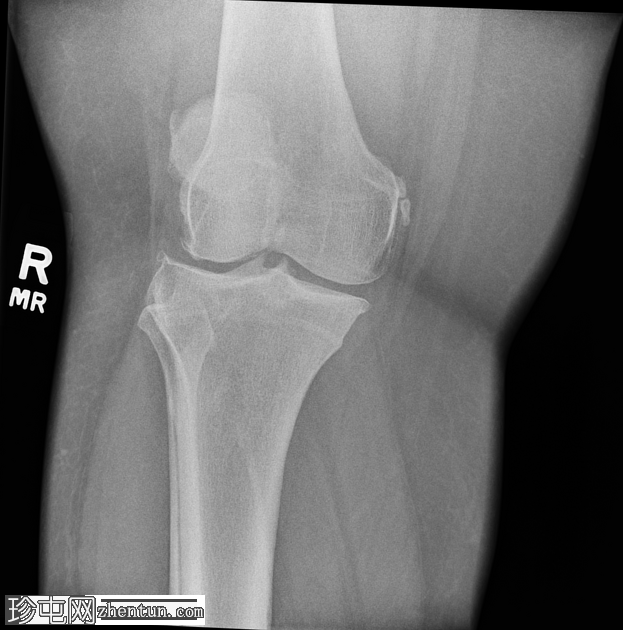

正位片

右膝中度骨关节炎(3级),表现为内侧胫股关节和髌股关节间隙狭窄,边缘可见骨赘、髌骨骨刺和胫骨棘突。

内侧副韧带近端附着处股骨内侧髁附近可见长圆形软组织骨化,提示为佩莱格里尼-斯蒂达(Pellegrini-Stieda)损伤。